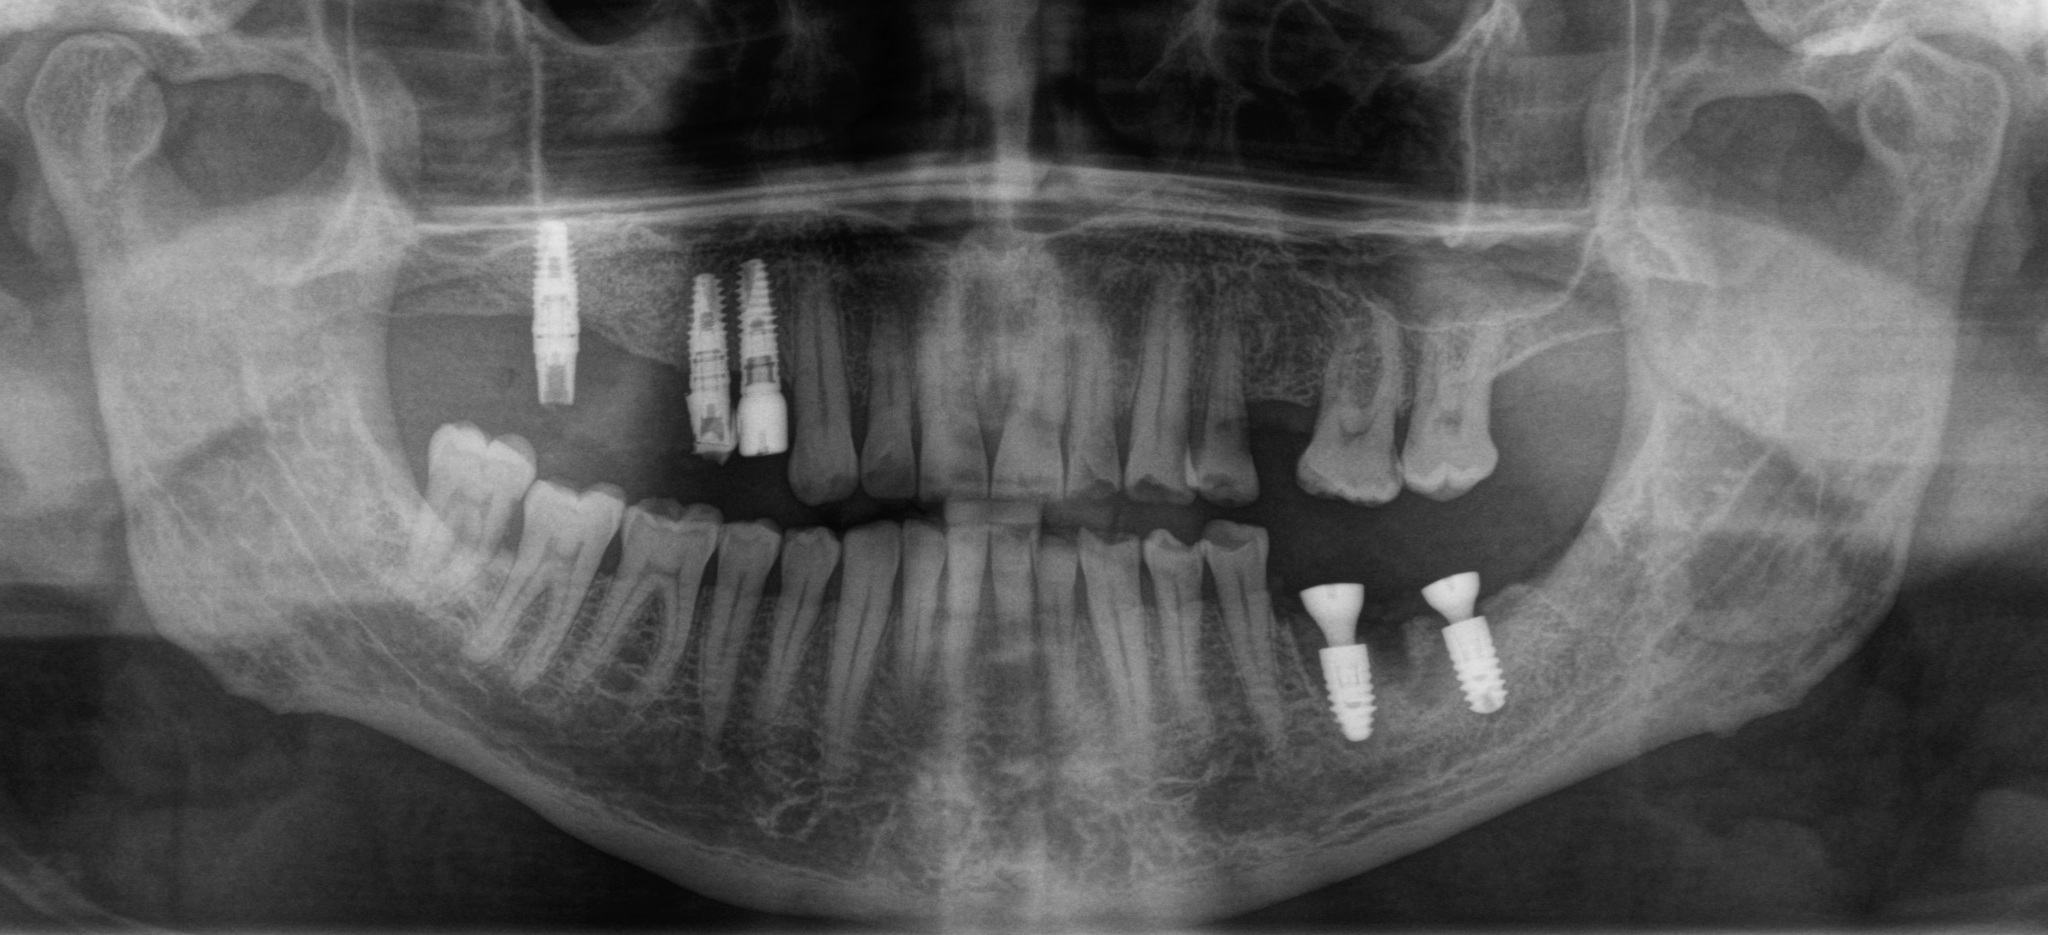

Было принято решение об удалении зуба и установке имплантатов в области 5 и 6 зубов:

Параллельно необходимо залечить 7-ку, пока нет коронок на имплнататах. Так подобраться к зубу проще.

Январь 2024. Наши дни. Установка постоянных безметалловых коронок слева сверху: